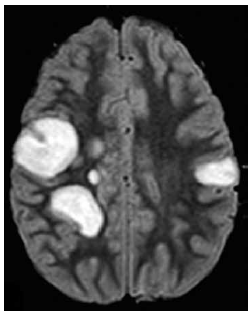

Menina de 9 anos de idade é levada ao pronto-socorro por sonolência e fraqueza muscular progressivas há 2 dias. Na avaliação, a criança se apresenta sonolenta, mas desperta aos estímulos vigorosos. Não responde aos comandos solicitados. Reflexos osteotendíneos são exaltados globalmente, e apresenta reflexo cutâneo plantar em extensão à esquerda e sem resposta à direita. O reflexo pupilar e o exame de fundo de olho são normais. Há 10 dias do início dos sintomas, ela apresentou quadro de infecção de vias aéreas superiores, a qual foi tratada com amoxicilina.

A imagem da ressonância magnética de crânio é mostrada a seguir.

O diagnóstico mais provável é